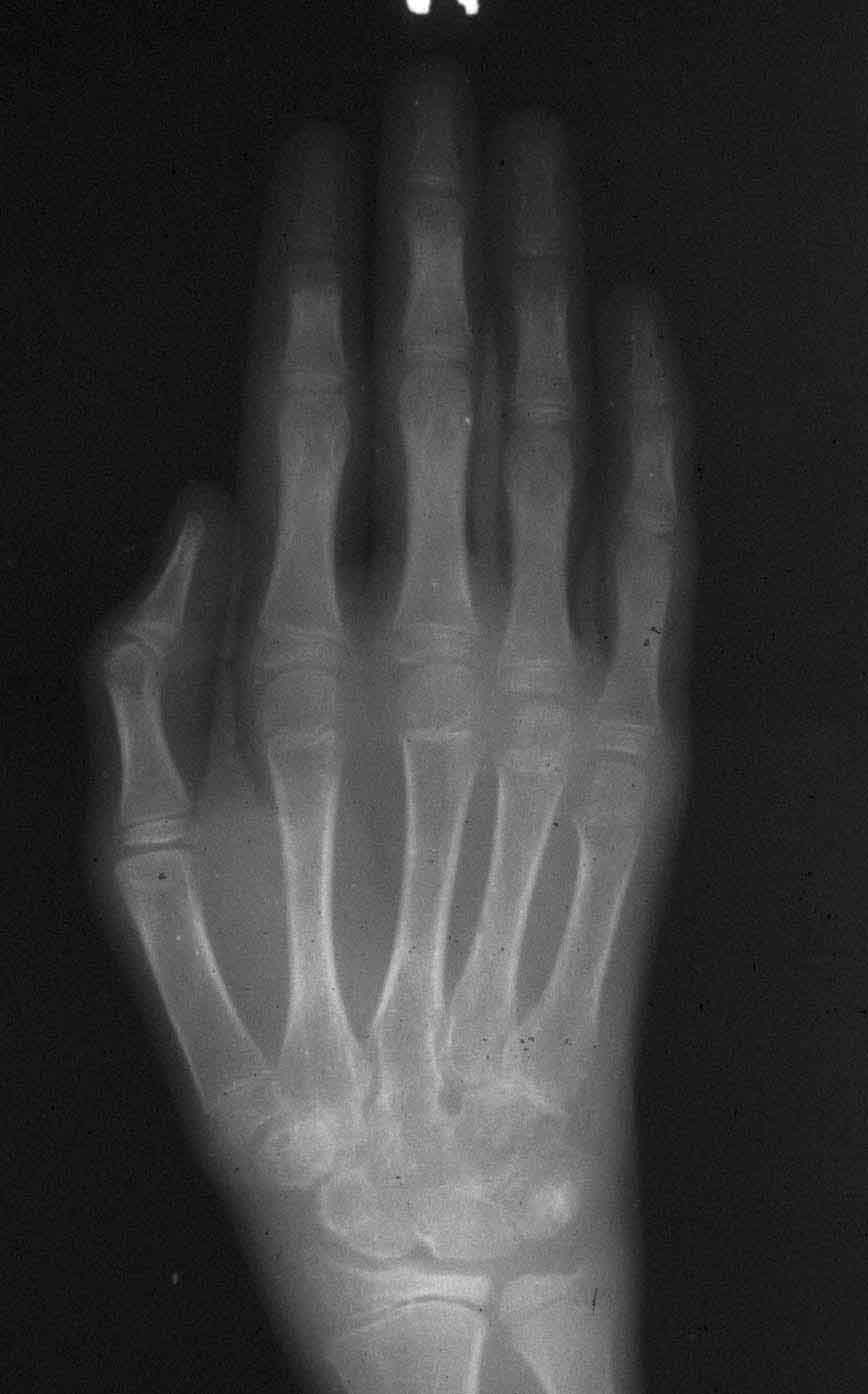

Title | Hand X-ray |

Subject | Polyarticular Juvenile Rheumatoid Arthritis |

Description | This radiograph of a child's hand with advanced polyarticular JRA shows subarticular osteopenia and fusion of the metacarpal bones. |